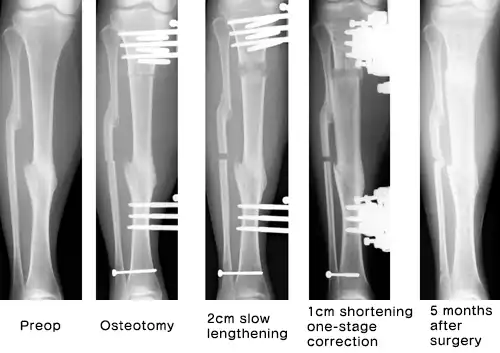

Slow extension + First-stage correction

- This is a case in which the right lower extremity has been twisted 40 degrees since the trauma and the bone fusion has been shortened by 1 cm. This disorder was corrected by bone regeneration with external fixation. After correction, the symmetrical correction can be seen.